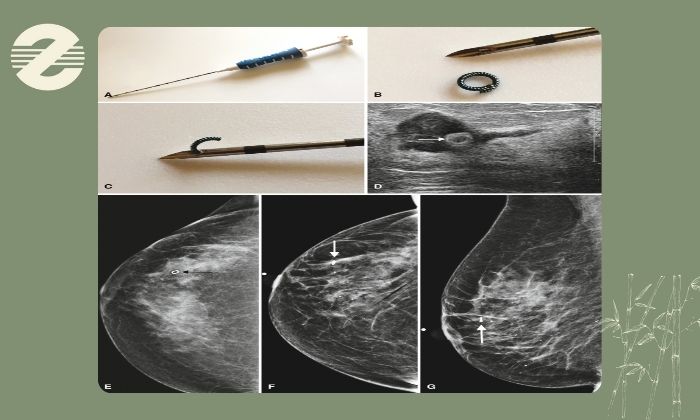

مرحله جایگذاری مارکر: پس از اثرگذاری بیحسی بیمار ممکن است فقط احساس فشار خفیف (نه درد تیز) را تجربه کند زمانی که سوزن یا ابزار در محل مورد نظر قرار میگیرد. در واقع اصلیترین حس در این مرحله حس ناشی از قرار گرفتن سوزن در بافت است نه درد ناشی از آسیب بافتی.

در واقع ناراحتی مارکرگذاری در مقایسه با برخی اقدامات دیگر مانند نمونهبرداری یا حتی گرفتن خون بسیار سبکتر است. بسیاری از بیماران این پروسه را با تجربه یک تزریق کوتاه یا انجام سونوگرافی چند دقیقهای مقایسه میکنند.